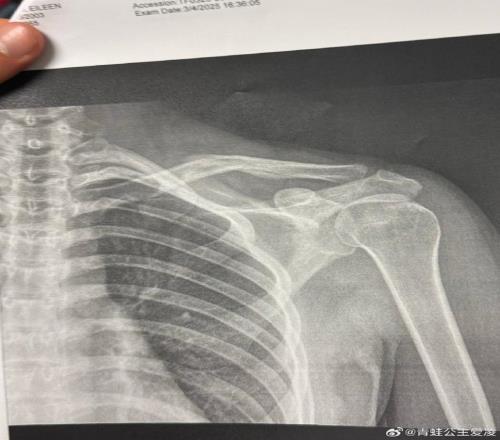

2025年3月9日,谷爱凌在交际网络上发布了一张X光片。

但事实是,谷爱凌的确在这个奥运周期的最终冲刺阶段不断阅历着伤病的摧残。2025年3月9日,谷爱凌在交际网络上发布了一张X光片。图片上,她右侧锁骨的裂缝清晰可见,配文只需一个心碎的表情符号,而这仅仅是“职业生涯最困难一年”的开端。